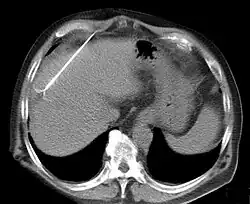

En la ablación por radiofrecuencia la destrucción se logra por aumento de temperatura debido al paso de la corriente de alta frecuencia (100 kHz-1MHz). Esta corriente no produce estimulación nerviosa ni muscular, sino solo calentamiento. Los procedimientos de ablación por radiofrecuencia se realizan bajo la guía de imágenes (por ejemplo de rayos X, tomografía computarizada o ecografía) por un anestesiólogo, o un radiólogo intervencionista, o un endoscopista gastrointestinal, o un electrofisiólogo cardíaco.